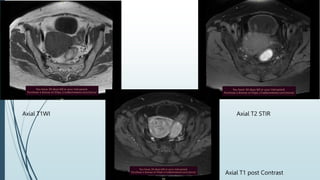

Sagittal T2WI Axial T2WI

Axial T1WI Axial T2 STIR

Axial T1 post Contrast

Coronal T2WI Coronal T2 STIR

 Uterus is bulky with diffuse junctional wall widening upto 13 mm

 Uterus shows homogenous post contrast enhancement. No

diffusion restriction seen in that widened junctional zone.